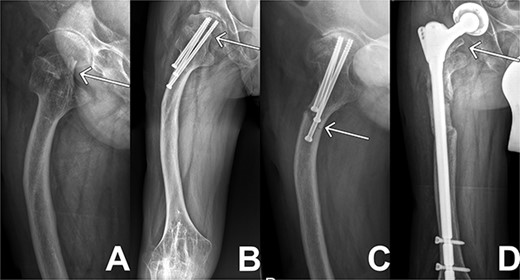

X-ray sequences of the right hip in different resolutions. (A) Representation of the medial femoral neck fracture before the first intervention as highlighted by arrow. (B) Osteosynthesis intervention of hip is highlighted by arrow few months after intervention. In addition, femoral deformity and knee rigidity are recognizable. (C) Periosteosynthetic fracture of the femoral shaft shortly before intervention. (D) Follow-up image of the inserted prosthesis material shows regular position.

Two months later, the patient was represented to the emergency department after stumbling with progressive pain being conservatively treated due to bland diagnostics. Despite the good progress as seen in follow ups exampled in Fig. 1(B), the patient presented after another two months with atraumatic intense immobilizing pain of the right hip. Radiological diagnosis revealed a periosteosynthetic femoral shaft fracture as seen in Figs 1(C) and 2. The indication for the need of a TEP was given.